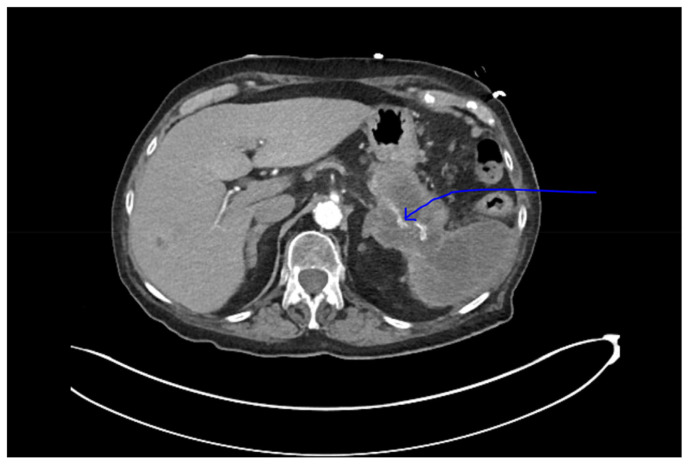

Pancreatic carcinoma has remained one of the leading causes of cancer-related mortality worldwide. Cancer originating in the head of pancreas is often detected early in the disease due to biliary obstruction resulting in jaundice. In contrast, cancer of the pancreatic body and tail remains indolent, presenting late with significantly increased tumor burden and distant metastasis. Unfortunately, a single laboratory screening study is neither sensitive nor specific for early detection of pancreatic cancer. In this report, we present a patient with longstanding diabetes incidentally detected to have pancreatic tail carcinoma while presenting with pulmonary embolism, emphasizing the need for pancreatic cancer screening studies in population with longstanding diabetes.